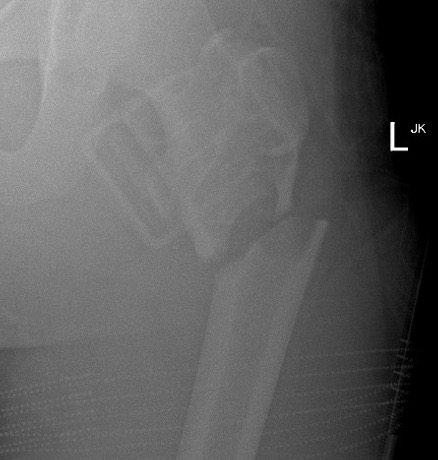

2. Femur

Want to prevent fracture and avoid morbidity / deformity

Options

Observe

Percutaneous treatment

- cortisone

- bone marrow aspirate / demineralized bone graft

Curettage and bone graft

ORIF